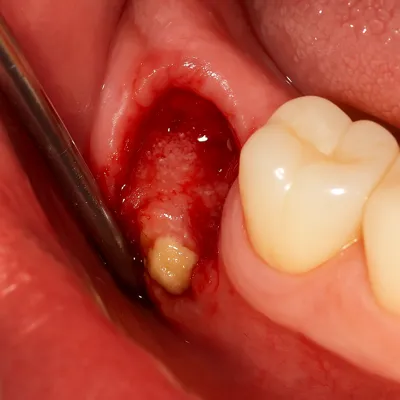

خارج کردن ریشه باقیمانده دندان با جراحی دهان و لثه

عفونت لثه و چرک داخل دهان پس از جراحی دندان

عفونت:

اگر بهداشت دهان رعایت نشود یا داروهای تجویز شده مصرف نشوند، احتمال عفونت وجود دارد. مصرف آنتیبیوتیک، شستوشوی ملایم دهان و مراجعه به پزشک در صورت بروز تب یا چرک، ضروری است. -